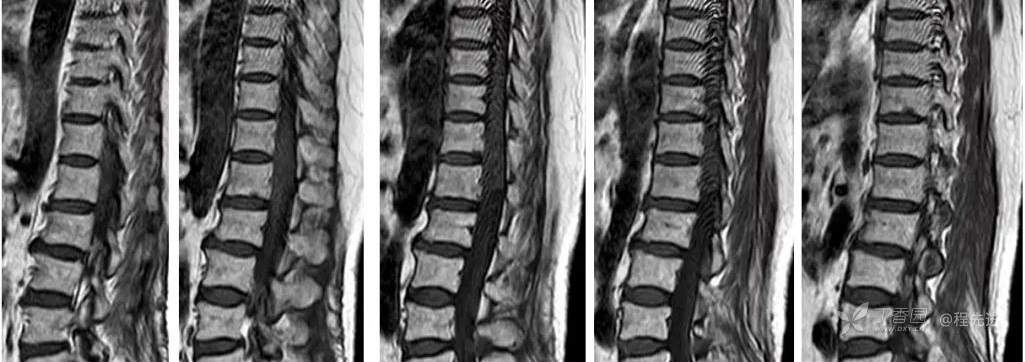

MR: